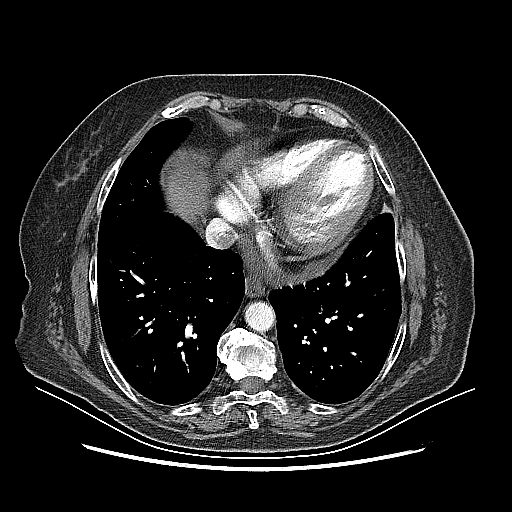

Original NATIVE CT scan (input)

No window - Raw intensity values

Reconstructed NATIVE CT scan (cycle consistency)

Original VENOUS CT scan

Generated VENOUS CT scan (A→B translation)